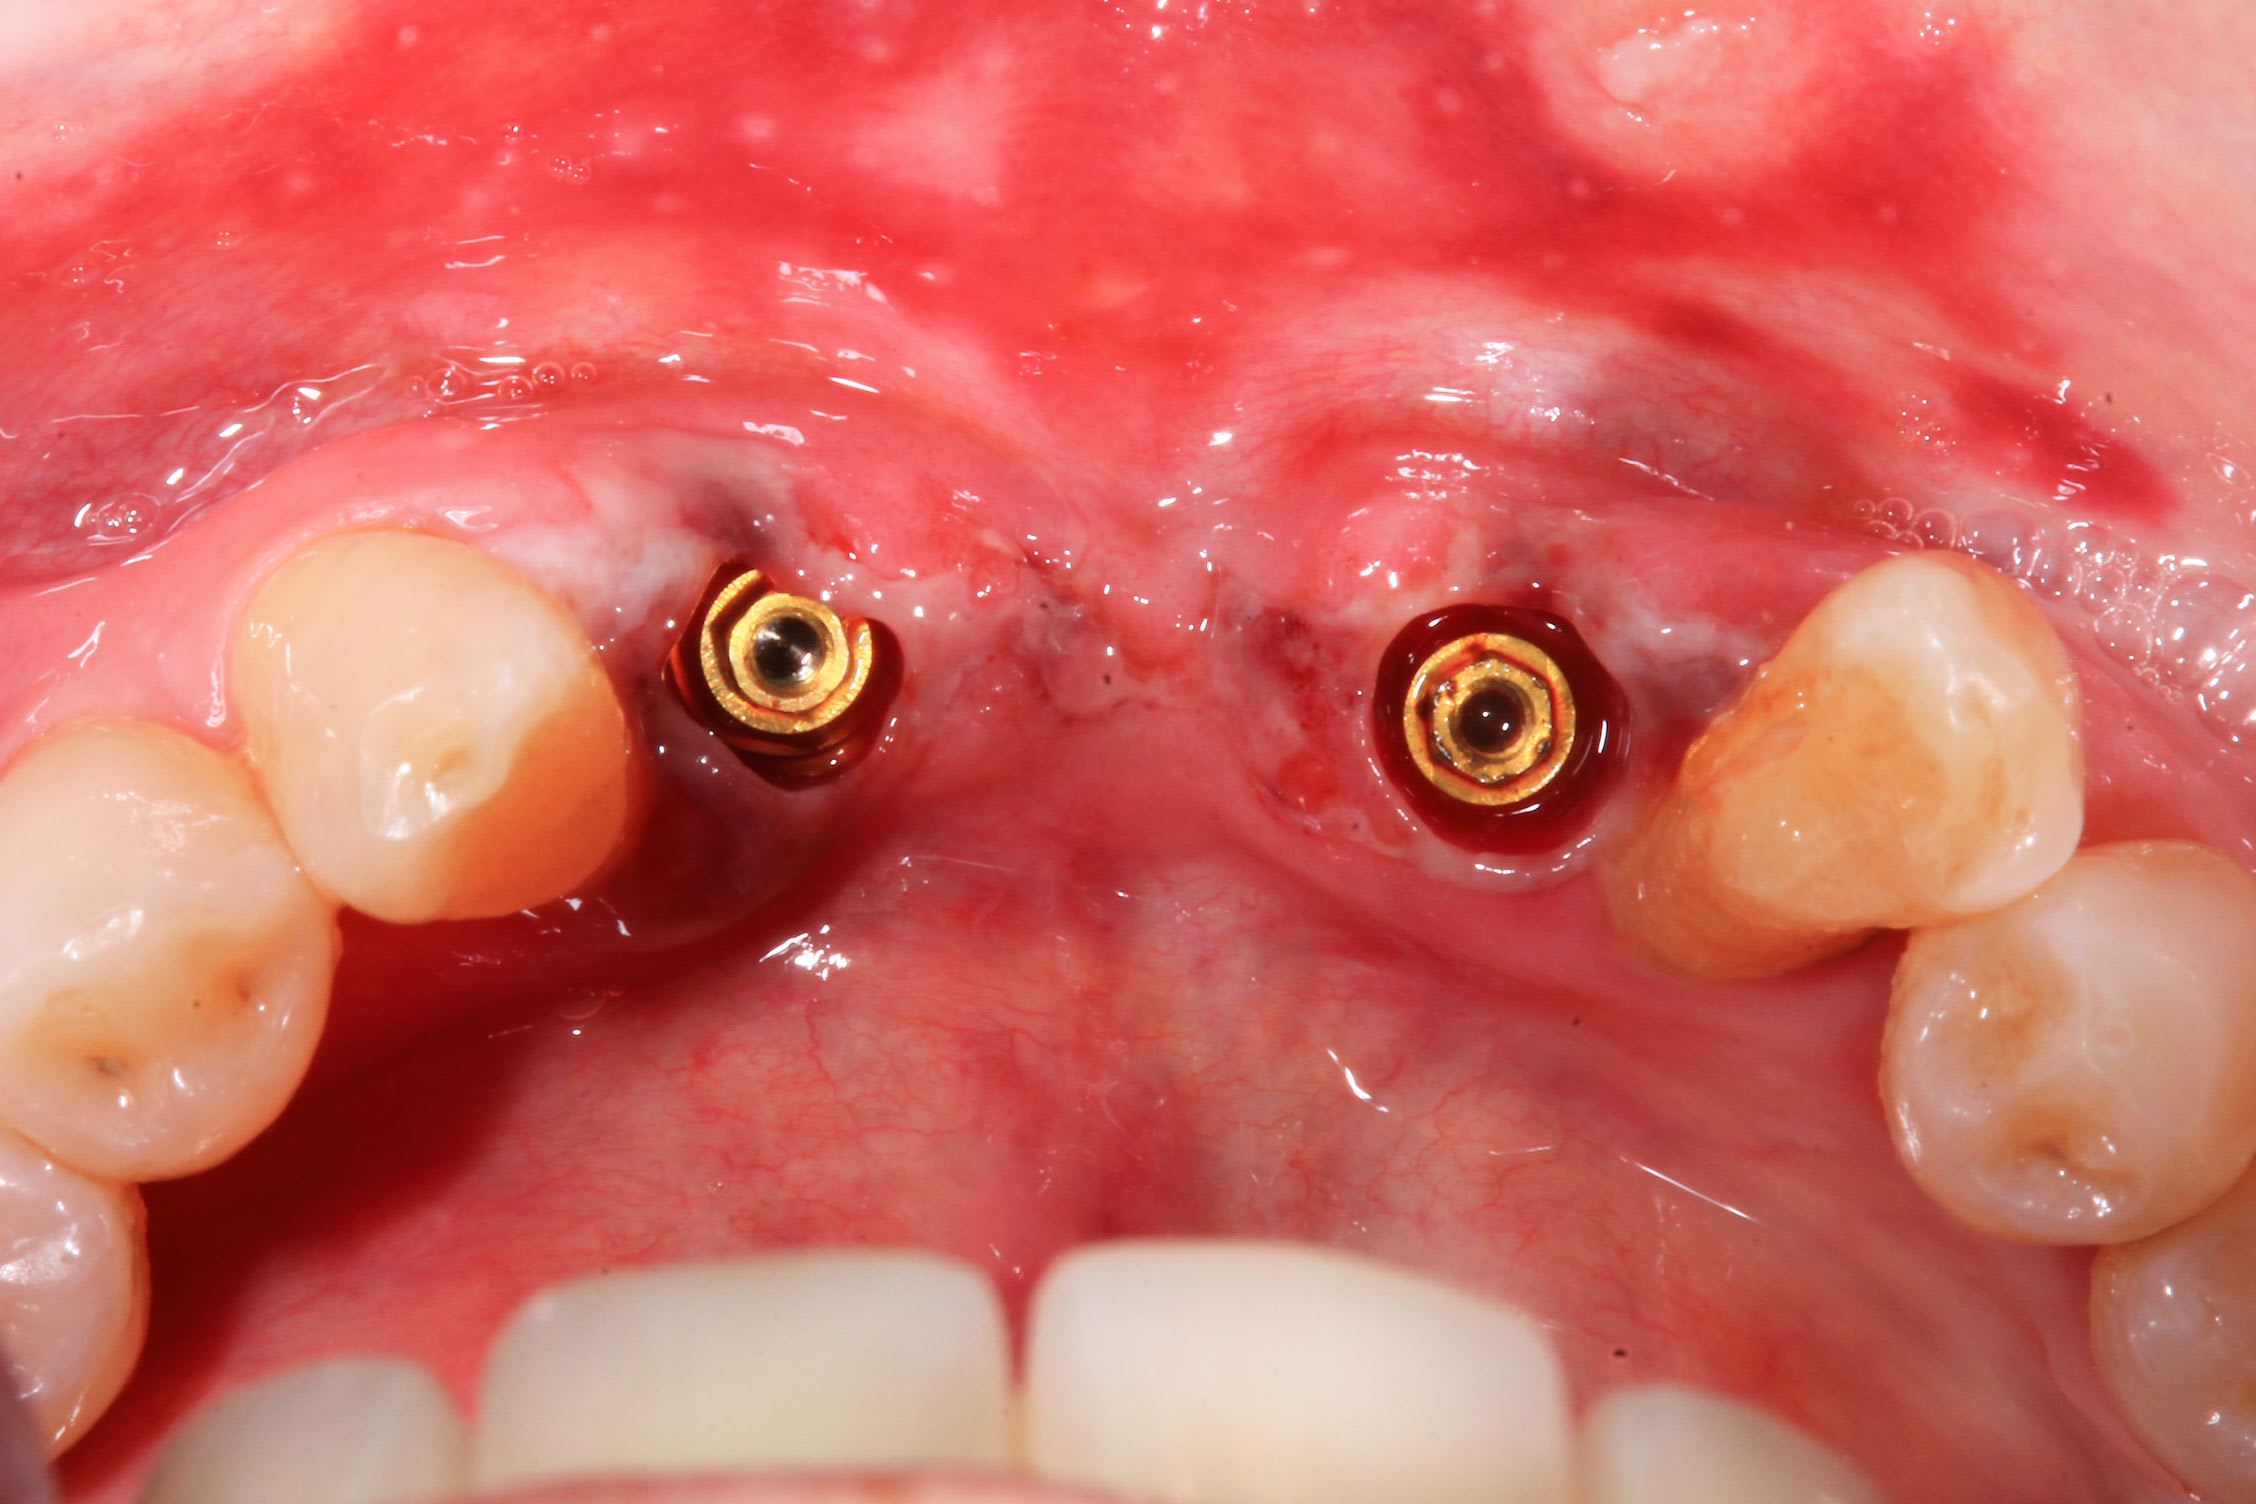

Autrement voici le prochain cas de pluton

Uzndgyh4j3jp73in0kayojbrs1b1 - Eugenol

Sekb7wvvo0auhvpkhvkytxt67oyf - Eugenol

pluton

06/07/2022 à 18h08

> Autrement voici le prochain cas de pluton

Et c'est toujours possible de venir découvrir avec moi....intervention le 21/07 prochain à partir de 9h00